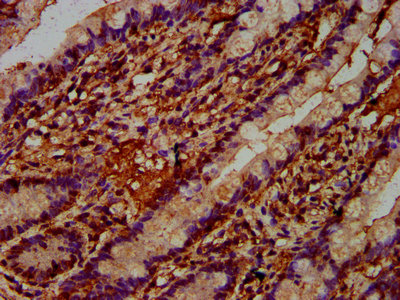

IHC image of CSB-PA887169LA01HU diluted at 1:400 and staining in paraffin-embedded human small intestine tissue performed on a Leica BondTM system. After dewaxing and hydration, antigen retrieval was mediated by high pressure in a citrate buffer (pH 6.0). Section was blocked with 10% normal goat serum 30min at RT. Then primary antibody (1% BSA) was incubated at 4°C overnight. The primary is detected by a biotinylated secondary antibody and visualized using an HRP conjugated SP system.